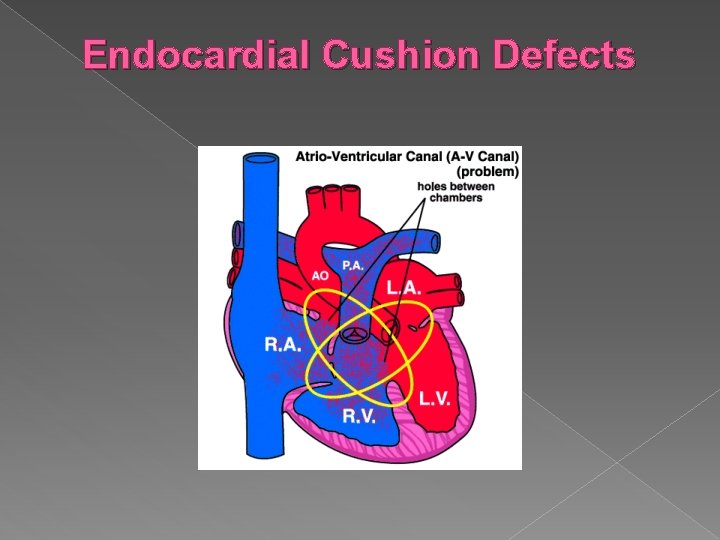

Other Cardiac Anomalies Some other conditions that can be diagnosed using ultrasound: Endocardial Cushion Defects › Atrial and ventricular septal defects resulting from failure of the common AV orifice to separate into mitral and tricuspid valves. Associated with an increased risk of Trisomy 21. Tetralogy of Fallot › Consists of four anatomic abnormalities: Large VSD, overriding aorta, pulmonary infundibular stenosis, right ventricular hypertrophy. Ebstein’s Anomaly � Downward displacement of the septal and posterior leaflets of the tricuspid valve

� Endocardial cushion defect is also called atrioventricular septal defect (AVSD). AVSD involves problems with the structure of the heart. The heart normally has 2 upper chambers (atria) and 2 lower chambers (ventricles). A normal heart also has 2 heart valves (the tricuspid and mitral valves) that separate the upper and lower chambers.

� In AVSD, there may be a large hole in the center of the heart where the wall (septum) joins the upper and lower chambers of the heart. The tricuspid and mitral valves may not be separate. Instead, there can be one large valve between the upper and lower chambers of the heart (common atrioventricular valve). The large opening in the center of the heart allows the oxygen-rich (red) and the oxygen-poor (blue) blood to mix. The heart pumps blood in a way that is not efficient and becomes enlarged.

An AVSD is the most common congenital heart defect found in children with Down's Syndrome, accounting for 50% of the total. � In its complete form there is a hole in the wall between the top chambers (atria) and a hole in the wall between the bottom chambers (ventricles), and one common valve between the two atria and the two ventricles. In the partial forms there may not be a hole between the bottom chambers (ventricles) or the mitral and tricuspid valves may not be joined together, but either or both may leak, known as valve incompetence. �

Endocardial Cushion Defects